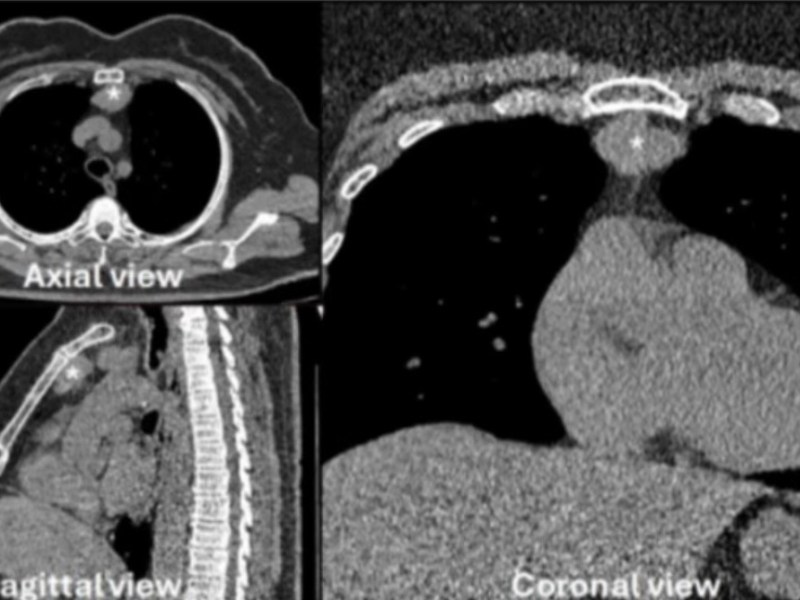

Il trattamento chirurgico del cancro del polmone con metastasi dei linfonodi ilari

Il cancro del polmone con metastasi dei linfonodi ilari rappresenta ancora uno stadio trattabile chirurgicamente. 😷L’intervento chirurgico consiste nell’asportazione del tumore e dei linfonodi alfine di ottenere la radicalita’ oncologica. I linfonodi sono adesi ai vasi e la loro asportazione può causare una lesione vascolare. 🤖La chirurgia robotica grazie alla visione tridimensionale ed ai movimenti…